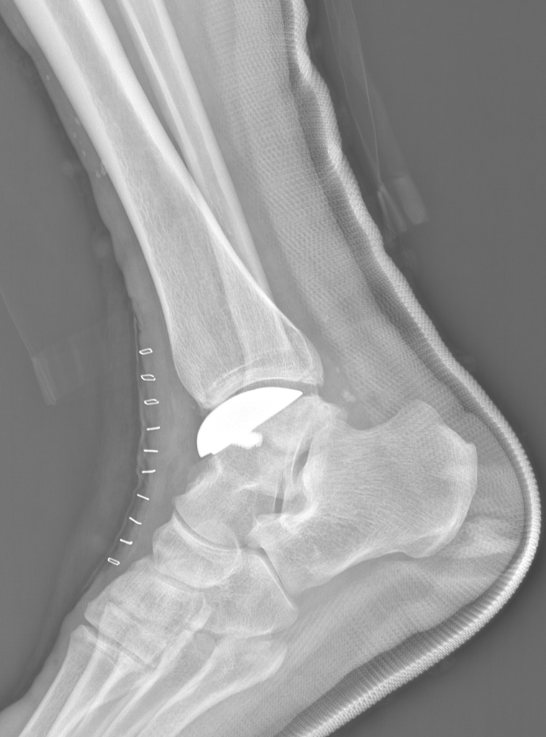

术后侧位X线

术后正位X线

武勇主任团队给他做了3D打印导板辅助下人工全踝关节置换术。

这种手术适合踝关节病严重的患者,通过替换病变的关节结构,能帮着缓解疼痛、恢复关节活动,让老人日常走路更自在些。